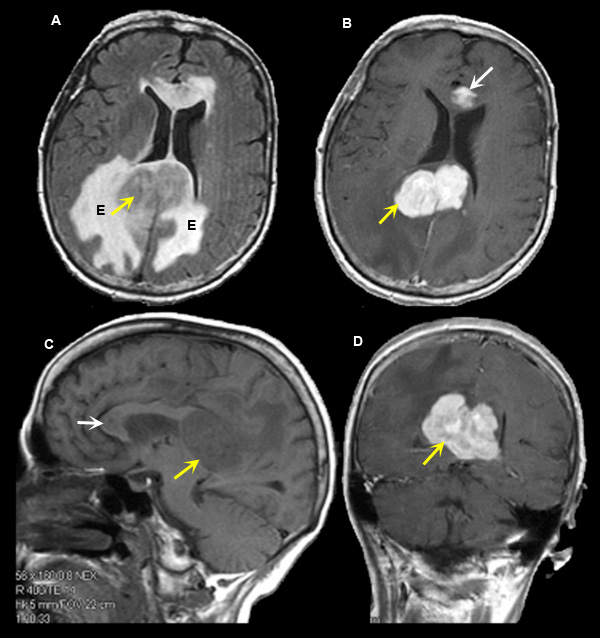

Lymphoma

Case 6:

Imaging findings: Figure 6

-

Intensely enhancing tumor is seen involving the posterior body of corpus callosum (yellow arrow in figs B, D), including smaller tumor involving the genu of corpus callosum (white arrow in fig. B).

- Tumoral edema (E in fig. A) surrounding the lymphoma is well appreciated on axial flair image as an area of bright signal intensity.

- Non-specific abnormality is seen in the pre-contrast sagittal T1 wtd. image (fig. C).

Final impression:

Lymphoma of the posterior body of corpus callosum.

Primary brain lymphoma often occurs in immunocompromised host. Common sites of involvement include corpus callosum, basal ganglion, thalamus and periventricular white matter.